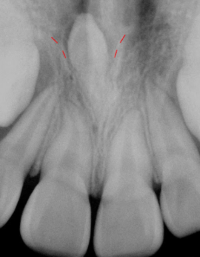

과잉치는 다양한 형태로 나타날 수 있으며, 가장 일반적인 형태는 앞니 사이에 생기는 "정중과잉치(mesiodens)"입니다. 이러한 과잉치는 치열의 배열을 방해하거나 치아 맹출 경로를 막을 수 있습니다.

과잉치의 존재는 주변 치아의 정상적인 발육을 방해할 수 있으며, 경우에 따라서는 통증을 유발하거나 치아 배열의 이상을 초래할 수 있습니다. 진단은 주로 치과 엑스레이를 통해 이루어지며, 치료는 과잉치의 위치와 환자의 상태에 따라 다릅니다. 일반적으로는 외과적 발치가 필요할 수 있으며, 이후에는 교정 치료를 통해 정상적인 치열을 유지합니다.

-상악 중절치 (Mesiodens): 가장 흔한 형태로, 상악 앞니 사이에 위치합니다. 대개 원추형으로 나타나며, 앞니 사이의 공간을 벌리거나 회전시킬 수 있습니다

-역위: 다른 치아와 반대방향으로 거꾸로 올라가는 방향으로 나는 과잉치를 의미합니다. (맨 위 사진)